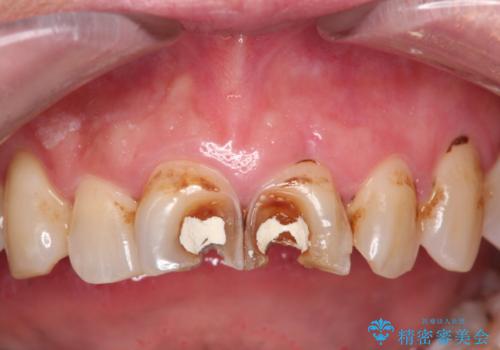

- 白い詰め物が急に外れたとの事で来院された患者様です。前歯にデンタルフロスも出来ず気になっていたとの事でした。

神経の検査をした所、問題ないので神経を残して被せ物の処置を行いました。